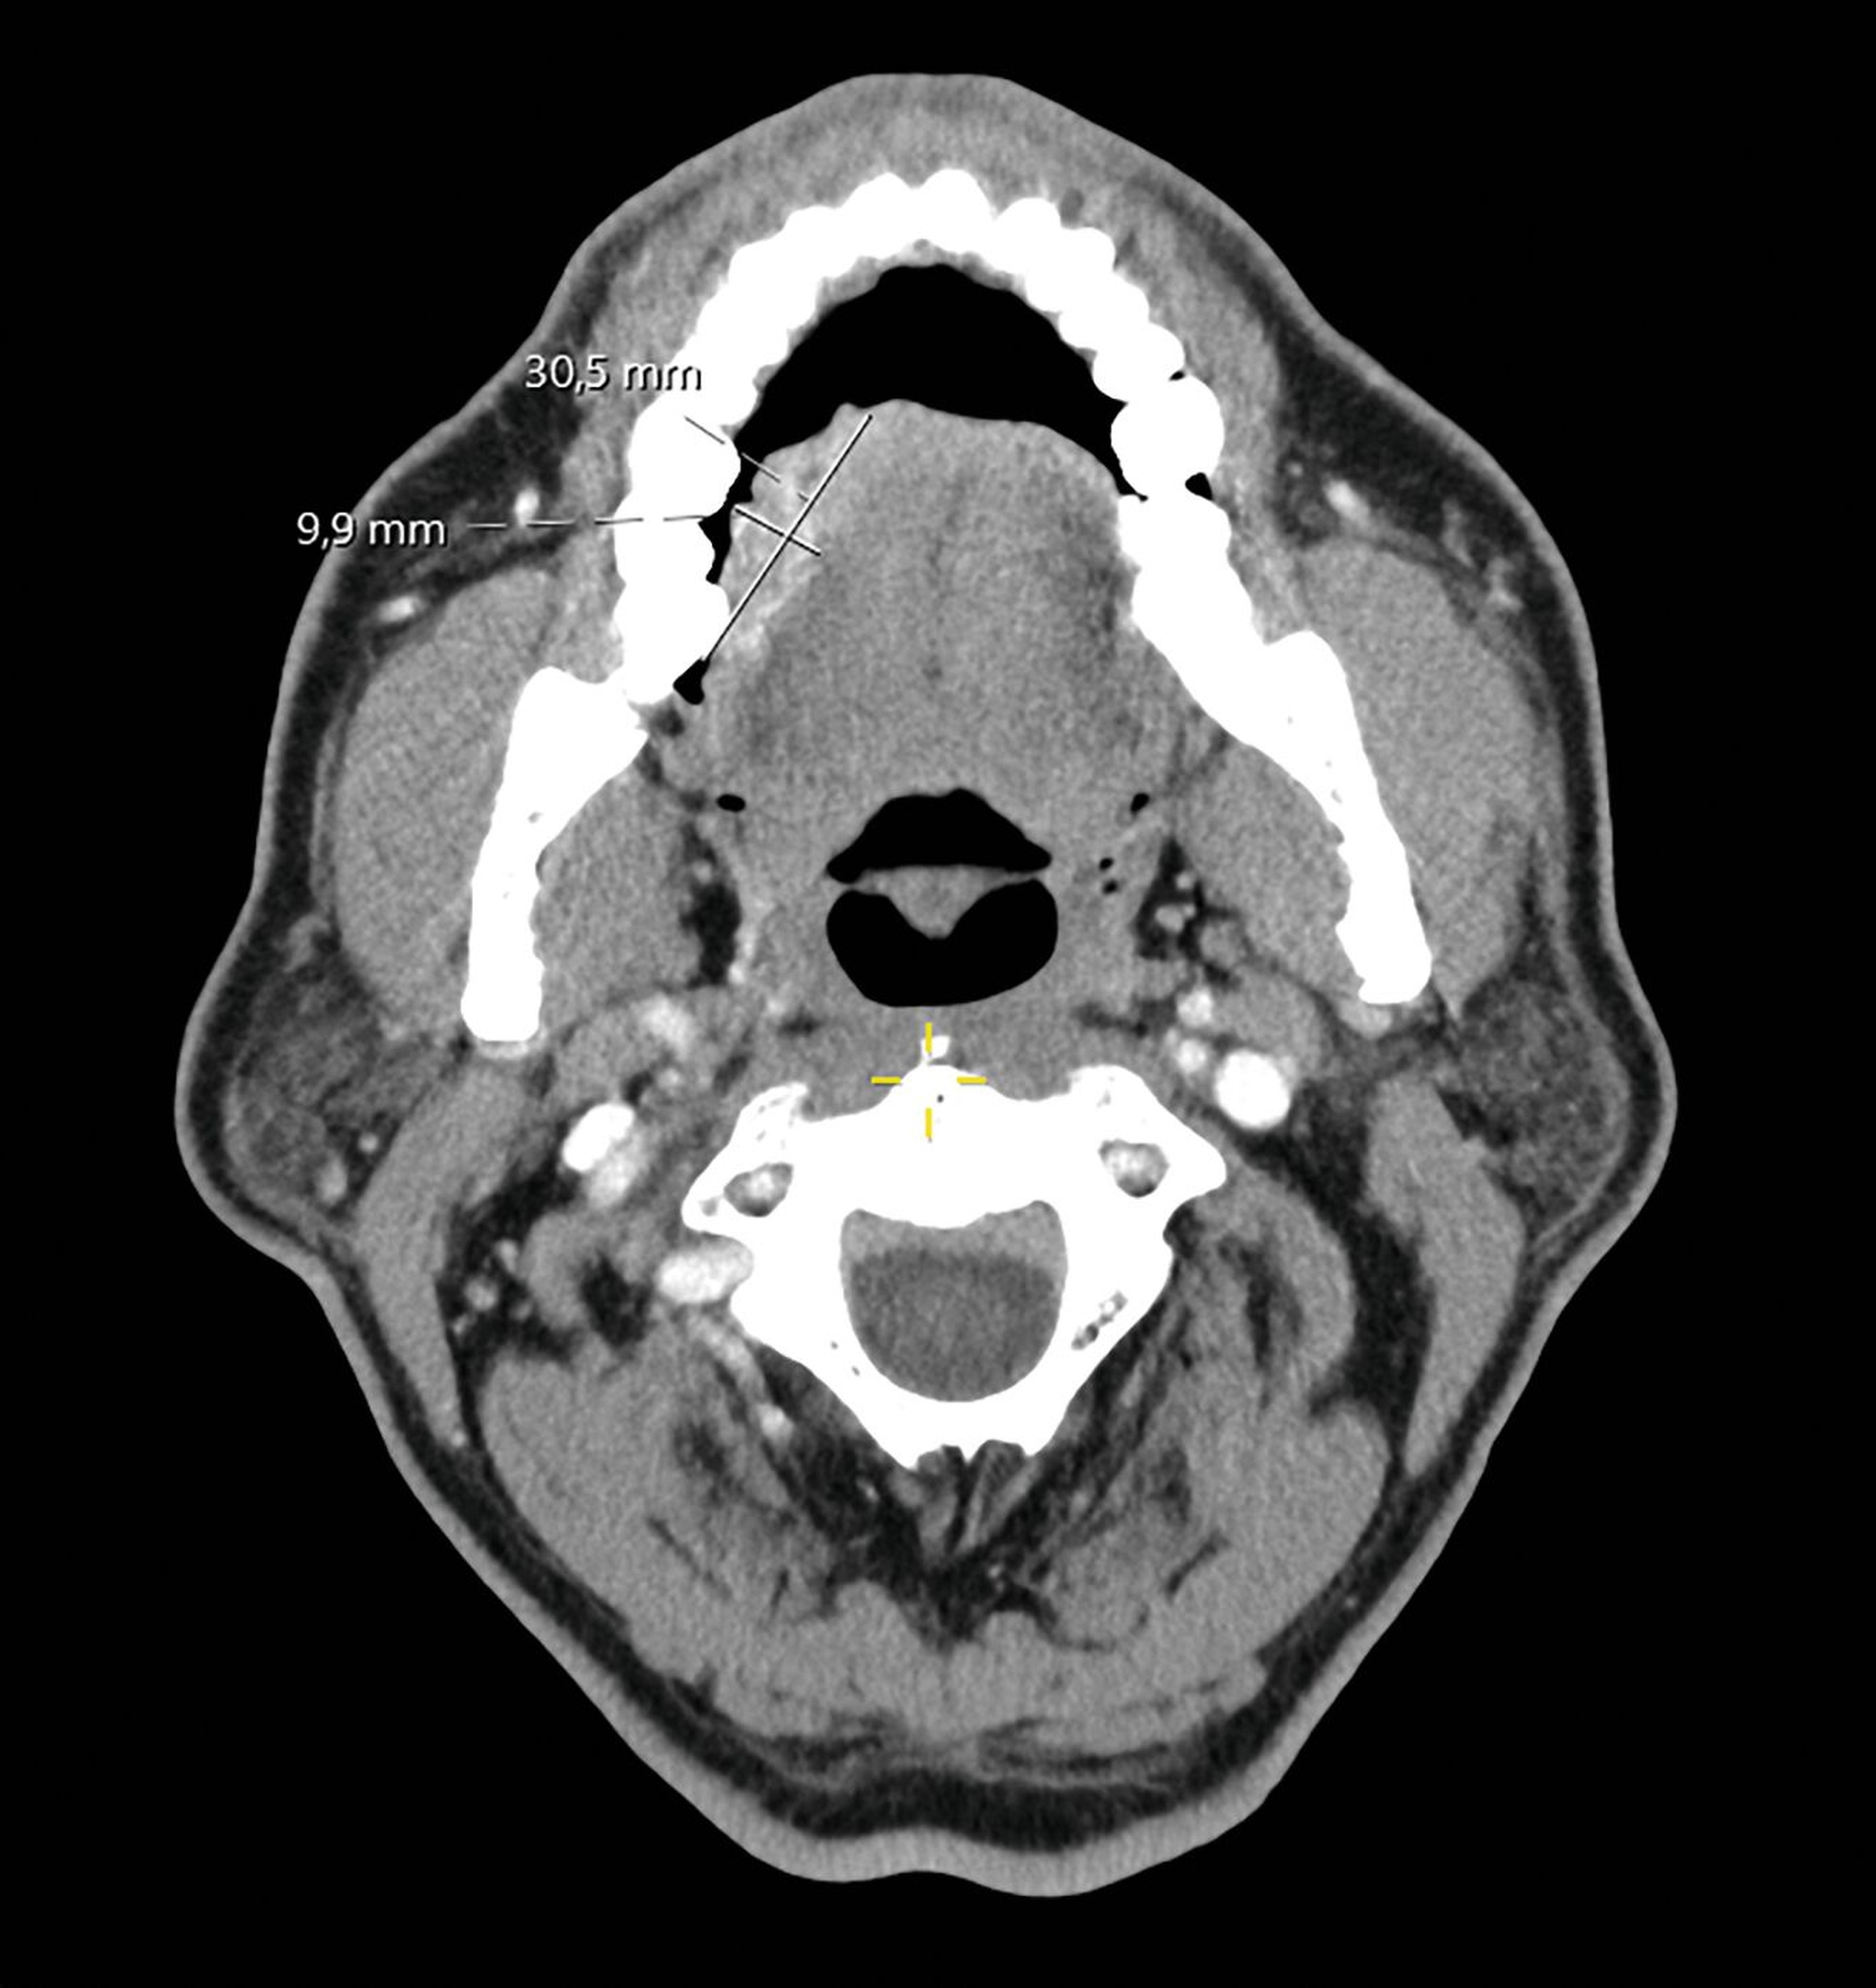

In der klinischen Untersuchung imponierte ein palpatorisch derber, exulzerierender Befund von circa 5 cm Größe am rechten Zungenrand ohne Mittellinienüberschreitung (Abbildung 1a). Die obligate Probeexzision ergab den histopathologischen Befund eines plattenepithelialen Papilloms mit erosiv-fluorider Entzündung ohne Hinweis auf Malignität. CT-morphologisch zeigte sich eine inhomogen vaskularisierte Läsion (28 mm × 17 mm × 10 mm) ohne Osteolyse oder pathologisch vergrößerte Lymphknoten (Abbildung 1b). Die empfohlene chirurgische Resektion wurde jedoch vom Patienten abgelehnt. Stattdessen entschied er sich nach Konsultation eines Heilpraktikers für einen homöopathischen Therapieansatz.